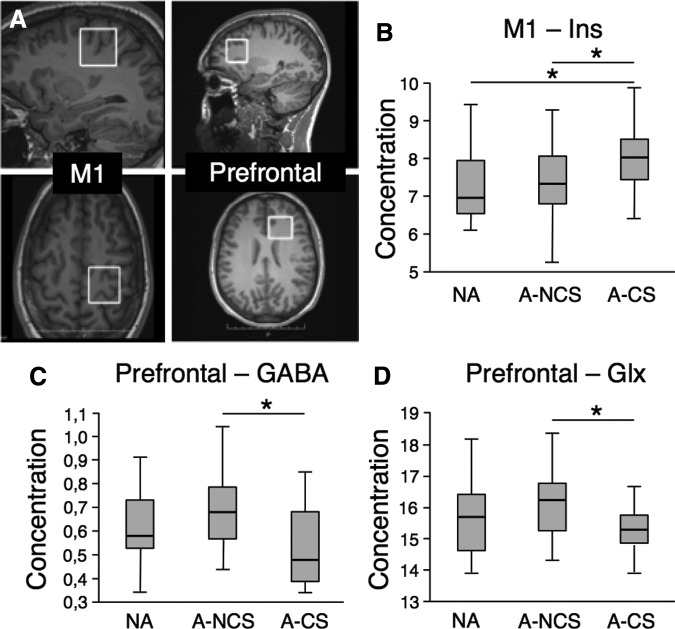

In the M1 (Fig. 2A), a significant group effect was found for mIns (n = 72; f = 3.76, p = 0.029), which was higher in the A-CS group compared with both NA (p = 0.029) and A-NCS (p = 0.016) groups (Fig. 2B). In the prefrontal cortex (Fig 2A), a significant group effect was found for GABA (n = 65; f = 4.32, p = 0.017; Fig. 2C), where concentrations were lower in the A-CS group compared with the A-NCS group (p = 0.005). A significant group effect was also found for Glx (n = 70; f = 3.15, p = 0.049; Fig. 2D), where concentrations were lower in the A-CS group compared with the A-NCS group (p = 0.016).

FIG. 2.

Magnetic resonance spectroscopy analysis. (A) Position of the voxels-of-interest in the left M1 and left prefrontal cortex. (B) mIns concentration in the primary motor cortex. (C) GABA concentration in the prefrontal cortex. (D) Glutamate and glutamine (Glx) concentration in prefrontal cortex. N-A, nonathletes; A-NCS, noncontact-sports athletes; A-CS, contact-sports athlètes ; GABA, gamma-aminobutyric acid.